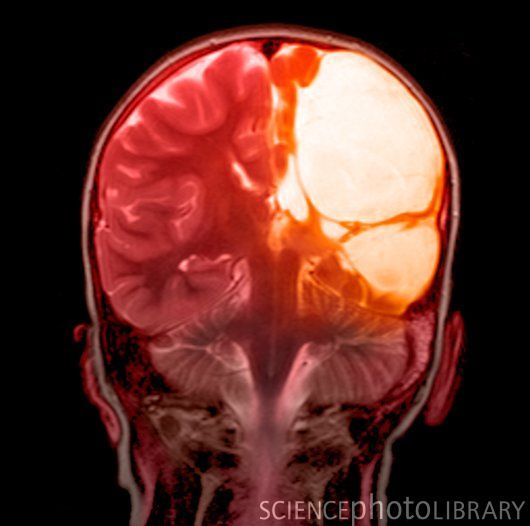

МРТ ребенка с ДЦП. Снимок в аксиальной проекции показывает поражения головного мозга с левой стороны: кистозную трансформацию гемисферы и обширную ишемию полушария в бассейне задней и средней мозговых артерий

При ДЦП МРТ помогает установить место и обширность поражения головного мозга, определить время повреждения. Указывающими на заболевание признаками являются:

- уплотнение и уменьшение белого вещества в объеме;

- атрофия долей мозга, чаще всего лобных и височных;

- разрастание глии;

- уплотнение (и нередко сращение с корой) оболочек мозга;

- увеличение подпаутинных пространств, особенно в передних отделах;

- растянутость желудочков;

- кистозные образования в коре больших полушарий;

- нарушение кровотока в интра-и экстракраниальных церебральных сосудах и т.д.